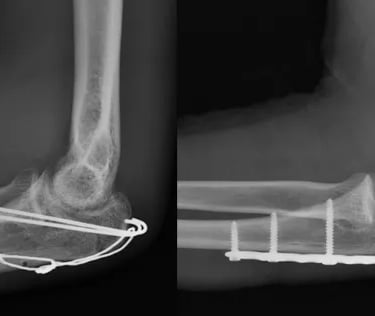

Fratura do Olécrano

O olécrano é uma parte da ulna, um dos ossos do antebraço. Ele se articula com o úmero no cotovelo. As fraturas desse local costumam ocorrer após queda sobre a mão ou traumas diretos sobre o cotovelo.